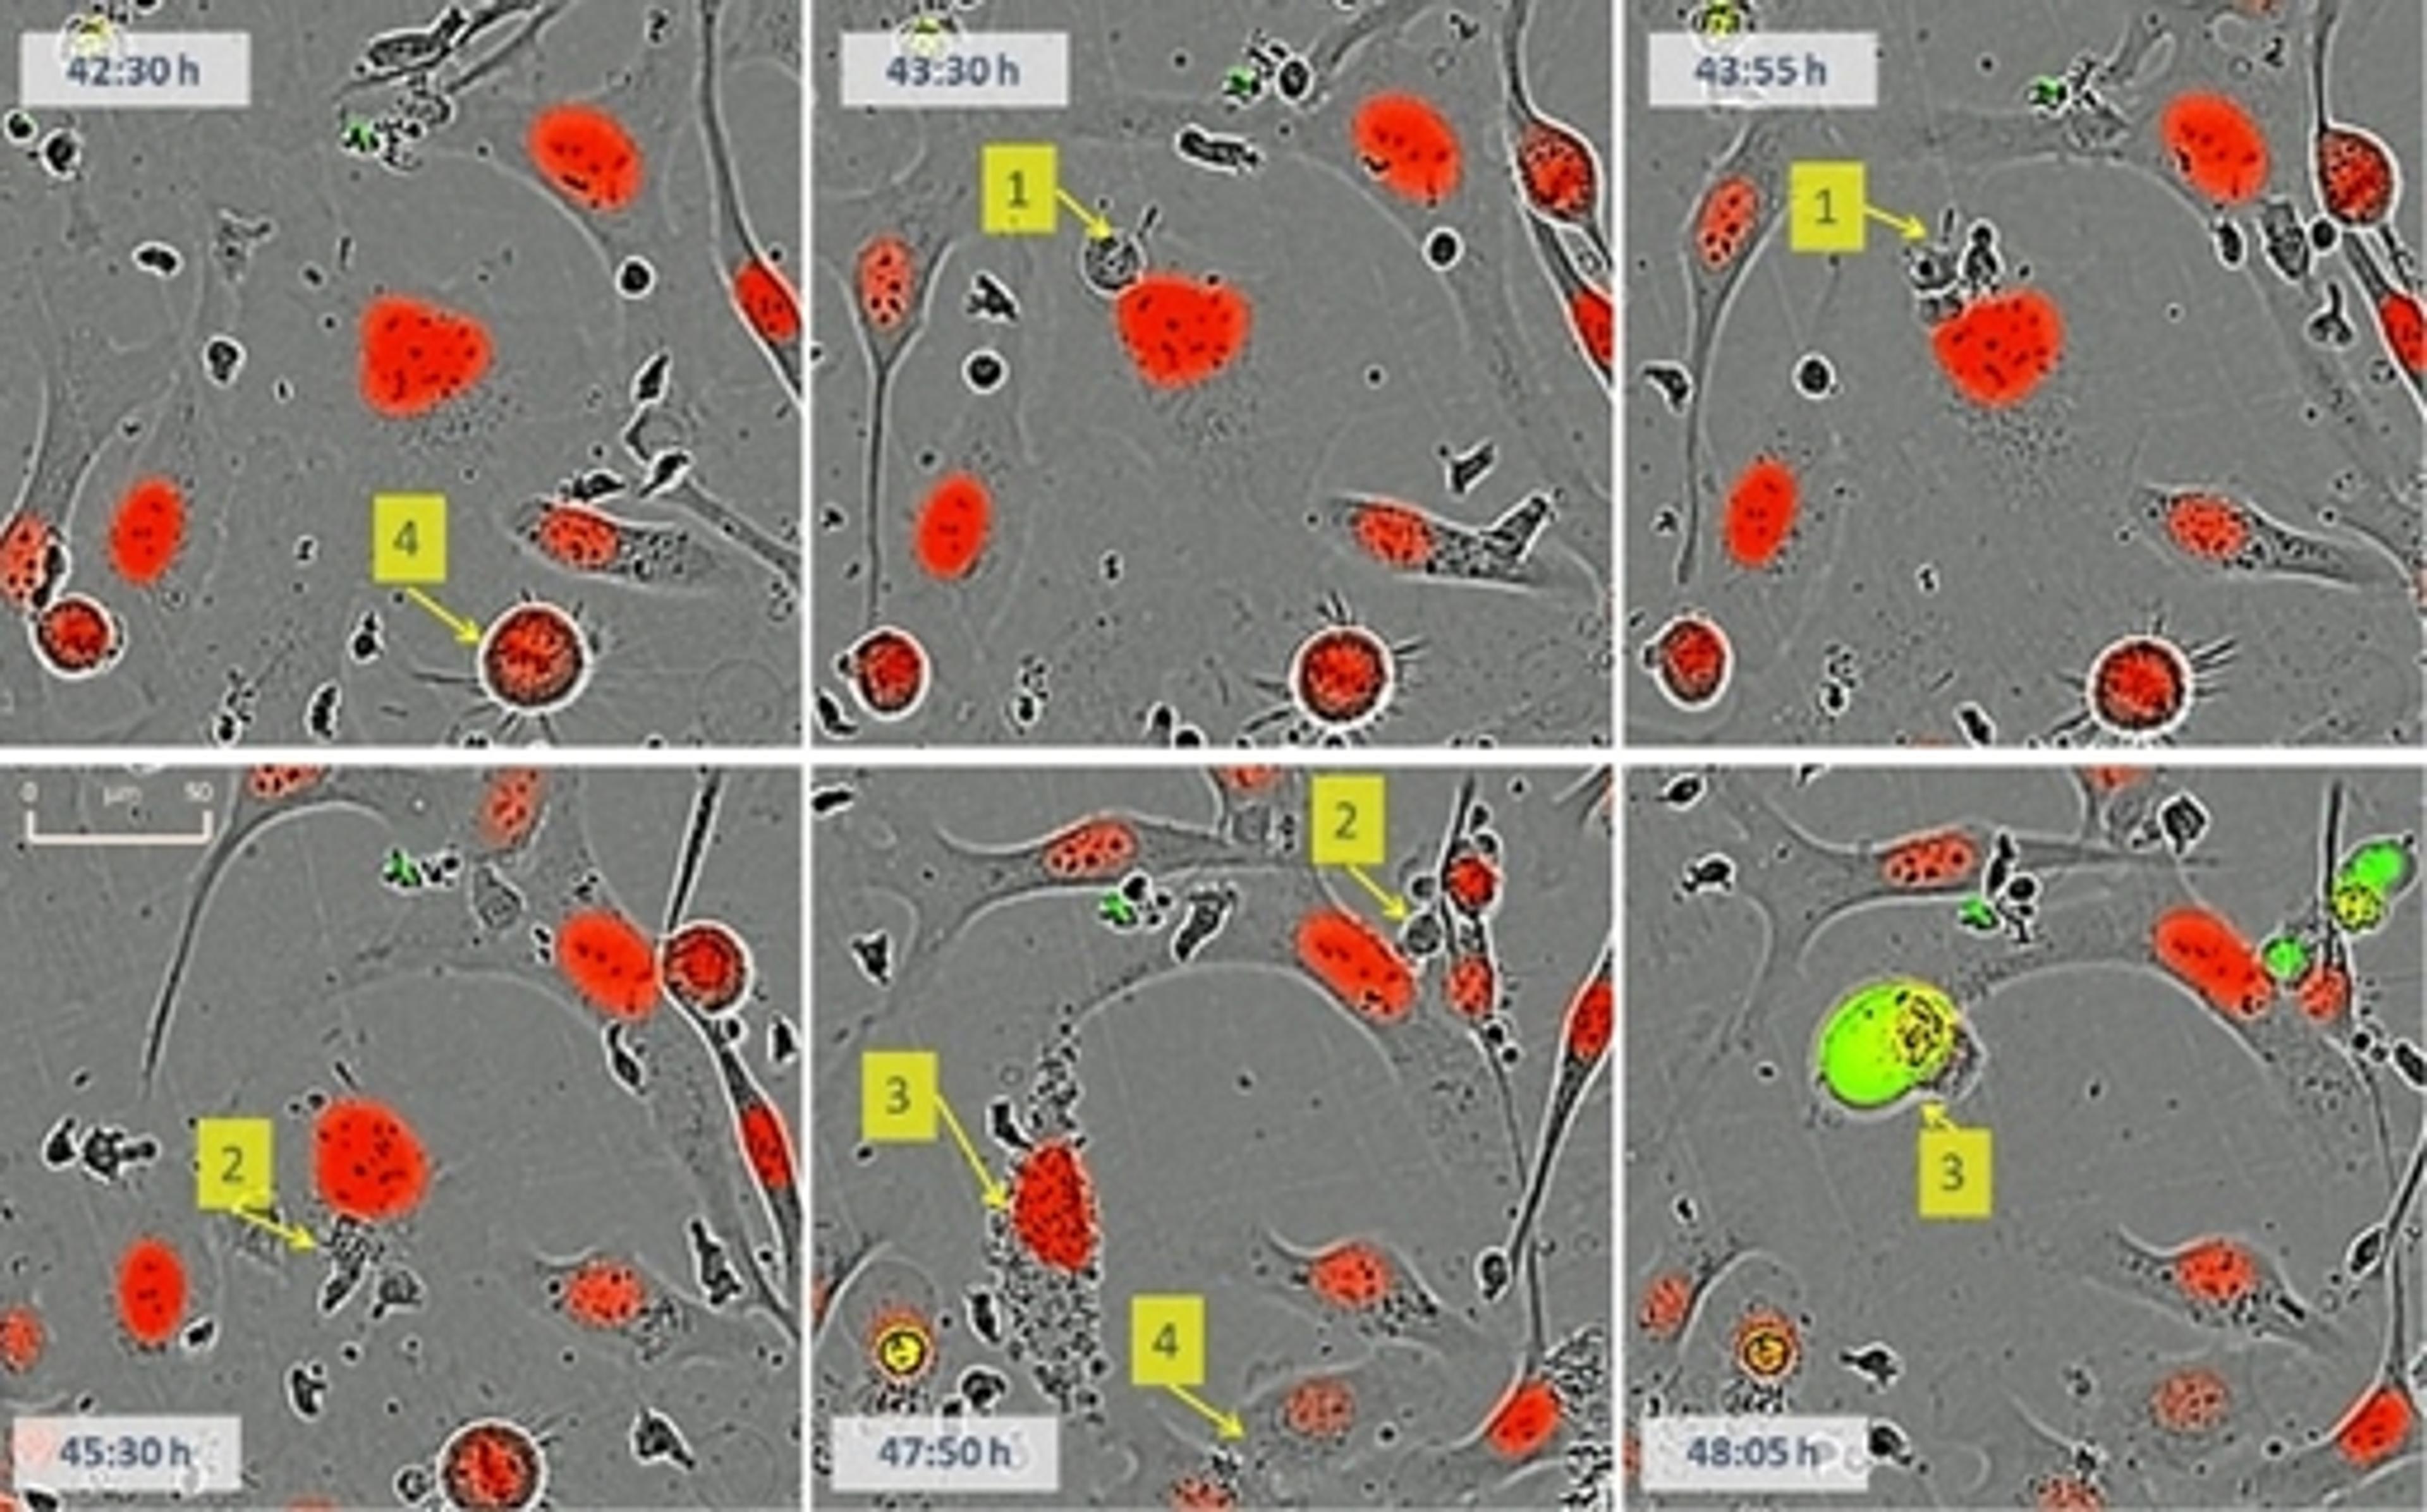

As a cancer researcher focused on developing and optimizing drug therapies, the Incucyte has revolutionized the way I track cancer cell behavior, assess drug efficacy, and uncover new therapeutic candidates. Traditional endpoint assays provide only static snapshots of cellular responses, often missing critical dynamic changes. The Incucyte overcomes this limitation by enabling real-time, continuous imaging of live cells, allowing for kinetic analysis of drug effects over days or even weeks. The system’s ability to capture both phase-contrast and fluorescence imaging in a label-free or labeled manner has been particularly valuable in monitoring cancer cell proliferation, apoptosis, and migration. I can now directly observe how drug-treated cells respond over time, rather than relying solely on indirect biochemical assays. This has been crucial in identifying dose-dependent responses, resistance mechanisms, and combination therapy synergies with unprecedented precision. Moreover, the automated data analysis tools streamline quantification, reducing variability and increasing reproducibility across experiments. With its non-invasive imaging approach, I can test multiple conditions simultaneously, improving throughput and accelerating drug discovery. The Incucyte has fundamentally changed how I conduct cancer drug research, providing deeper insights into treatment efficacy and enabling faster, more informed decisions in the development of novel cancer therapies.

Change can happen in an instant. Whether simply assaying cell health or more complex processes like migration, invasion, or immune cell killing, see what your cells are doing and when they do it. Incucyte® instruments, proprietary assays and reagents provide you with the ability to gain new insights into biological processes via real-time, quantitative analysis of live cells.

Conventional approaches to cell analysis only capture a single time point, enabling only single-point and end-point measurements, and cells are perturbed or destroyed as part of the assay process. Incucyte® systems offer the advantage of performing live-cell analysis without ever having to displace cells or disrupt their surroundings. The system automatically and continually collects and analyzes images throughout the course of an experiment while cells remain unperturbed in a physiologically relevant environment. Furthermore, Incucyte® accommodates multiple users and applications seamlessly and combines information-rich, image-based analysis with the convenience and throughput of microplate assays.

- Complex immune-tumor cell interactions

- Apoptosis (caspase 3/7 for live-cell imaging)

- Cytotoxicity

- Immune response – Immune cell killing